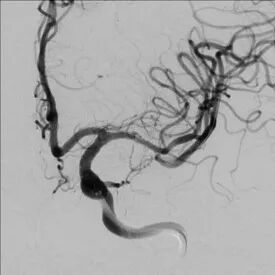

全脑及病变处不同体位造影:狭窄处成形好,未残余明显狭窄,左大脑中动脉主干及各分支显影好。

导丝怎么扩【载药时代 球扩天下】NOVA DES®颅内药物球扩支架在大脑中动脉重度狭窄中的应用——济南市第四人民医院使用体会一例!_https://www.jmylbn.com_新闻资讯_第13张

导丝怎么扩【载药时代 球扩天下】NOVA DES®颅内药物球扩支架在大脑中动脉重度狭窄中的应用——济南市第四人民医院使用体会一例!_https://www.jmylbn.com_新闻资讯_第14张